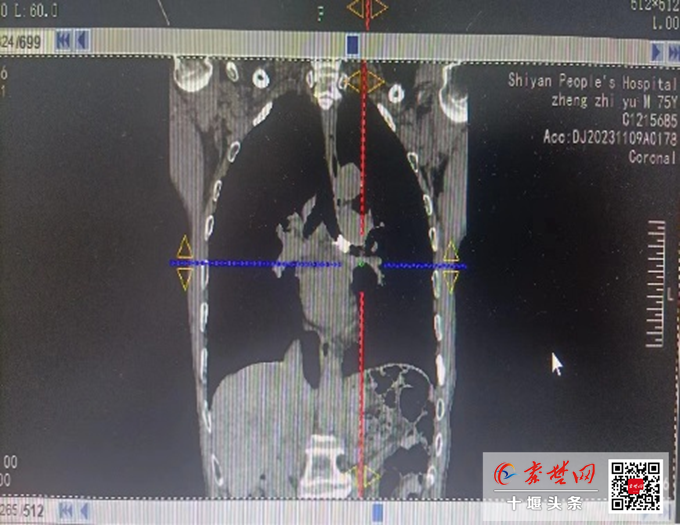

聽了黃大爺?shù)那闆r介紹后,朱建勇主任立即為其安排了相關(guān)檢查。胸部CT顯示,黃大爺“左主支氣管內(nèi)見(jiàn)約1.0×1.2×1.6cm結(jié)節(jié)狀不規(guī)則致密影,遠(yuǎn)端合并支氣管擴(kuò)張、阻塞性肺炎”。考慮到患者年老體弱,左主支氣管已被完全堵死,異物大,滯留時(shí)間久,貿(mào)然取出異物可能在氣道內(nèi)二次脫落及發(fā)生大出血、氣管瘺等風(fēng)險(xiǎn)。呼吸中心介入團(tuán)隊(duì)積極組織討論,制定了安全有效的手術(shù)方案及風(fēng)險(xiǎn)應(yīng)對(duì)策略。